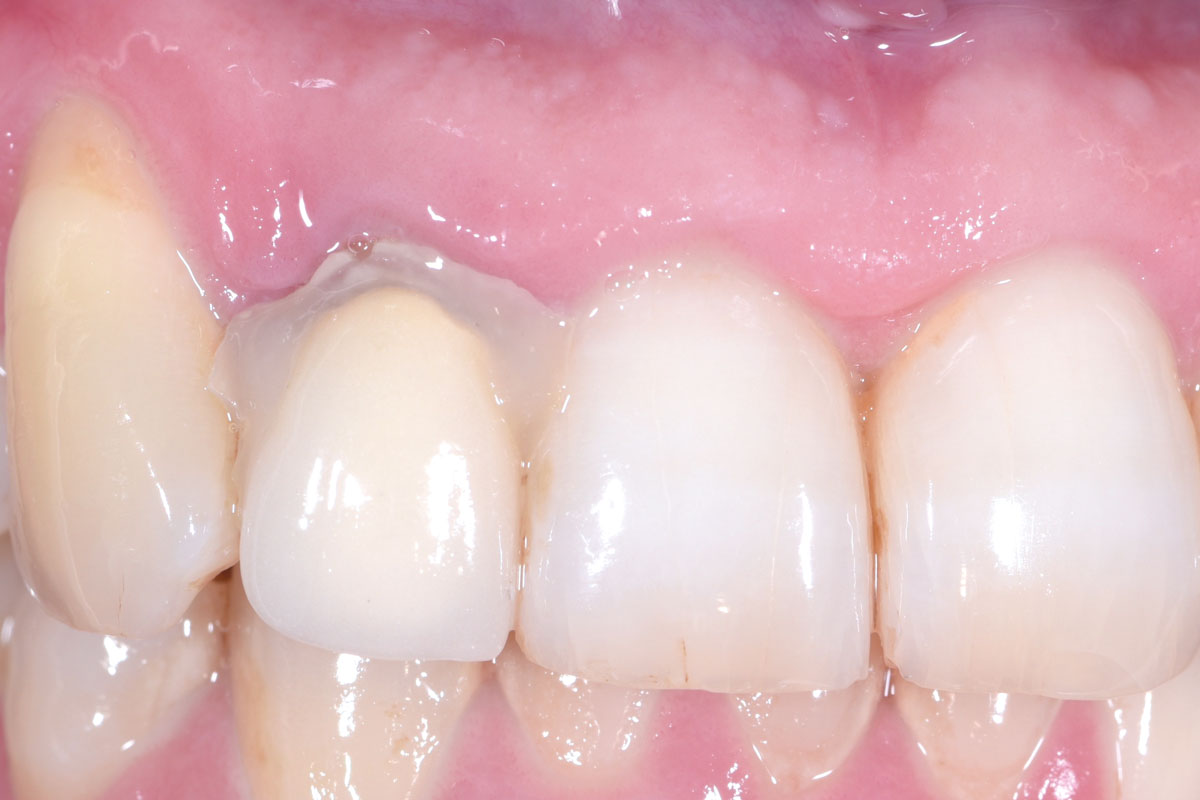

01/13 - The patient presented with a terminal fracture of the crown tooth number 12

Immediate implant placement in the maxilla with contour GBR - Dr. K. Loukas